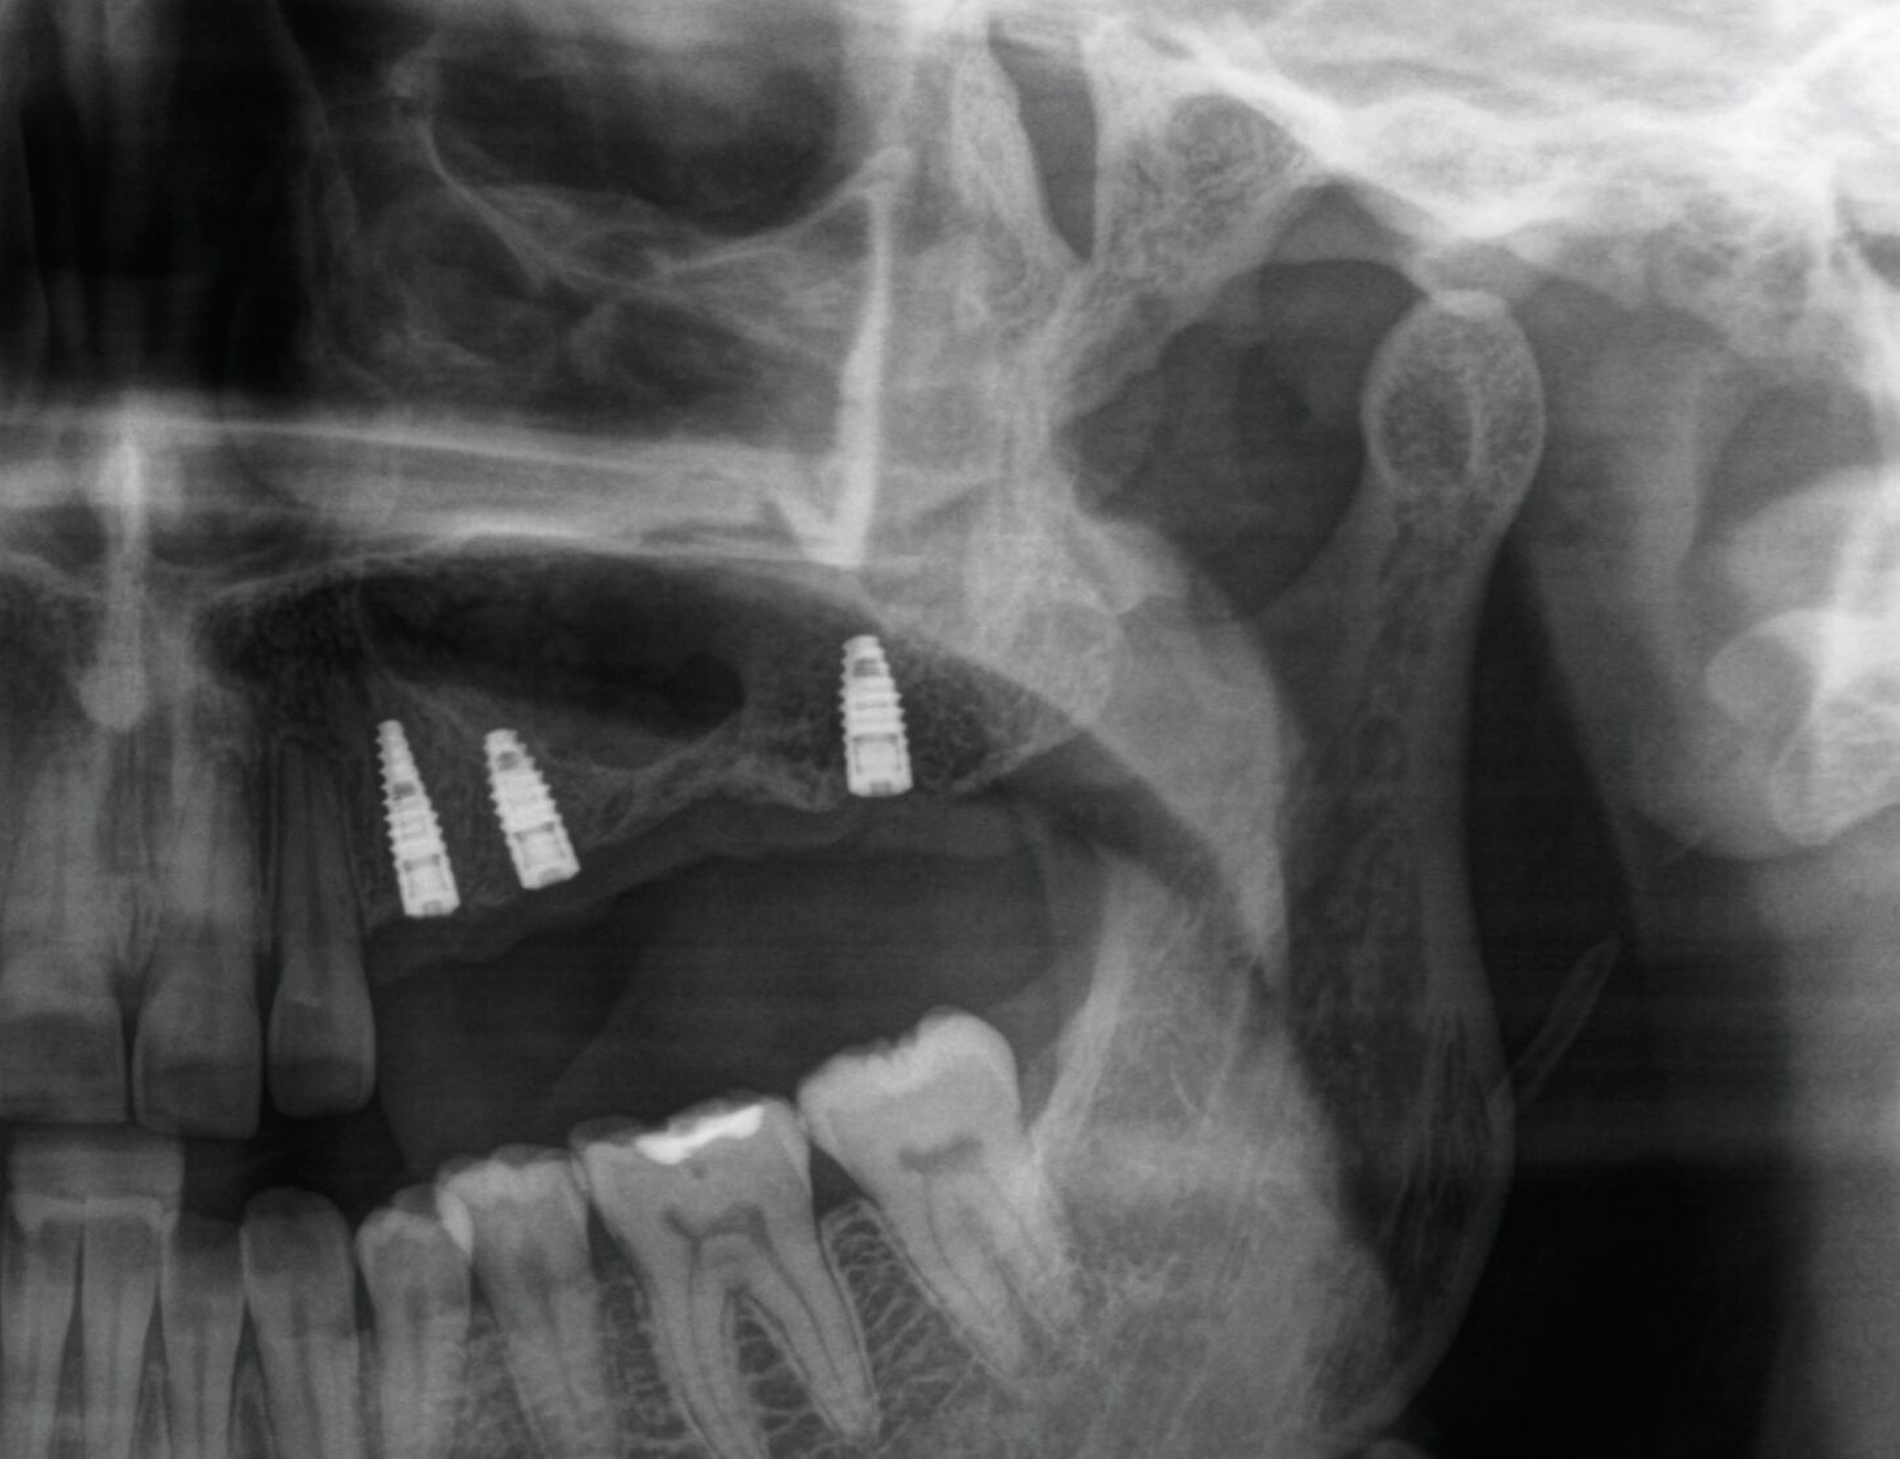

Eine 35-jährige Patientin stellte sich immer wieder mit rezidivierenden Schmerzen der linken Gesichtshälfte bei mehreren Ärzten vor. Die Beschwerden bestanden seit Jahren. Schon im Vorfeld waren mehrfach bei chronischer Sinusitis eine Kieferhöhlenrevision sowie eine Infundibulotomie linksseitig erfolgt. Regelmäßig kam es zu erneuten eitrigen Entzündungen. Die fraglichen Fokuszähne des zweiten Quadranten 24–27 waren vor einigen Jahren entfernt worden (Abbildung 1). 2017 war eine komplikationslose implantologisch-prothetische Versorgung der Freiendsituation erfolgt (Abbildungen 2 und 3).